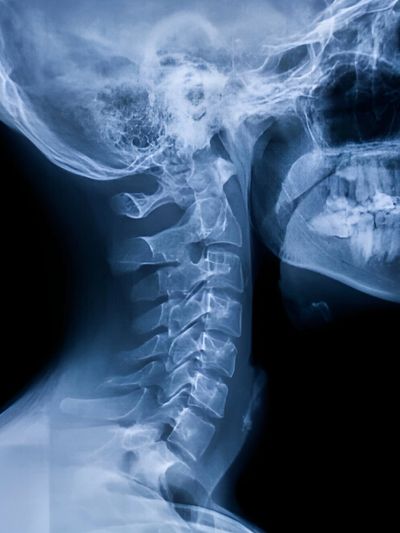

At Kamego Chiropractic, we offer digital X-rays to better understand the cause of your pain and ensure your care is safe and effective. X-rays allow us to evaluate spinal alignment, identify underlying issues, and determine the most appropriate approach to treatment.

In some cases, X-rays are necessary to rule out underlying conditions, assess alignment, or determine whether certain treatments are appropriate. Not every patient requires X-rays, but when they are needed, they provide valuable information that helps guide your care safely and accurately.

After your X-rays are taken, Dr. Kamego will review the images with you and explain any findings in clear, straightforward terms. You’ll understand what is being seen, how it relates to your symptoms, and what it means for your care moving forward.